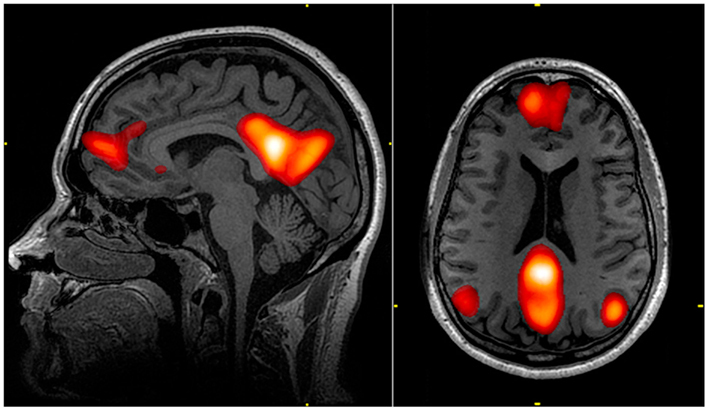

La soustraction des modifications observées dans le cerveau lors de l'exécution de la tâche, d’avec celles correspondant à l’état de repos étaient censées refléter les activations liées à cette tâche spécifique. Sauf que Raichle fait observer qu’un « repos » du cerveau n’existe pas, à proprement parler. Et que la consigne est passé aux sujets d’études « à présent, ne faites rien », n’est jamais appliquée littéralement. Si je ne dois rien faire… ben, je pense. A rien, mais, de fait, à rien de particulier. C’est-à-dire que dans cette machine, allongé, sans rien à faire, je m’ennuie, et je pense à rien de spécial. Raichle montrait alors qu’un cerveau qui ne fait rien, qui n’est engagé dans aucune tâche spécifique, active cependant un réseau incroyablement stable et reproductible, comprenant des aires cérébrales distribuées dans les régions frontales et pariétales, qu’il appelle le réseau du mode par défaut (« default mode network », DMN) parce qu’il constitue, en quelque sorte, l’écran de veille de notre matière grise (4).